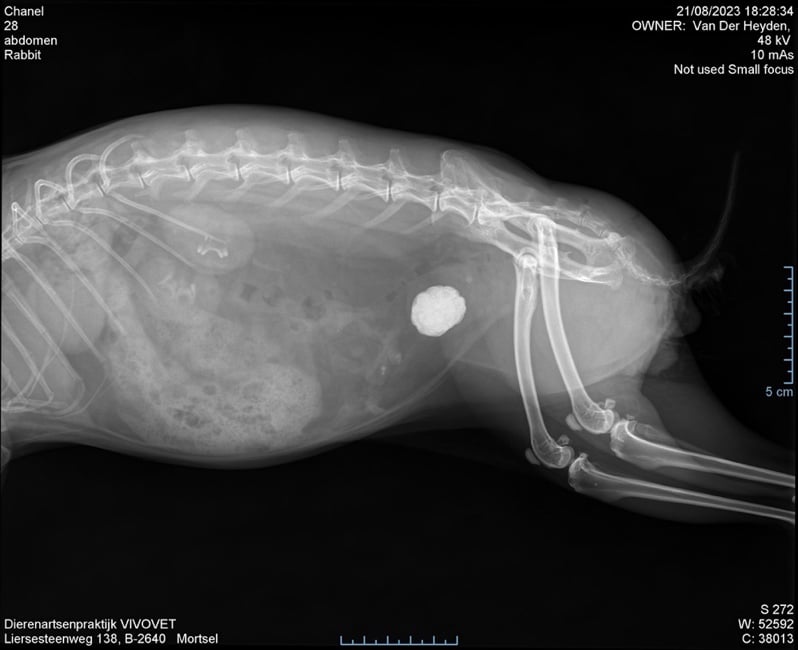

Uit het klinisch onderzoek bleek al snel dat haar buik heel gevoelig was ter hoogte van de blaas. Haar blaas was heel groot en voelde hard aan. Bijkomend was het konijntje ok veel te zwaar ten gevolge van haar sterilisatie 1,5 jaar geleden. Er werd besloten om met behulp van een RX een blaassteen uit te sluiten. Konijnen met obesitas zijn namelijk gepredisponeerd voor het ontwikkelen van blaasstenen. In combinatie met haar klachten was hier een grote kans toe.

Met behulp van de RX opname was de diagnose snel gesteld. Er zat een grote blaassteen die zorgde voor veel ongemak en pijn.